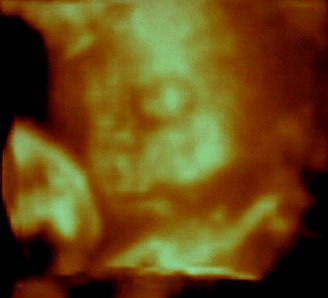

És íme, a 4D-s sztárfotó, amit már rég ígértem (kicsit állítgattam az eredetin, így talán jobban kivehető):